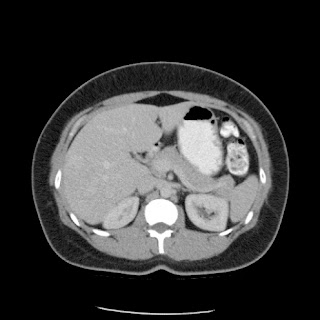

Paciente de 66 años con antecedente de pancreatitis, tomografía control.